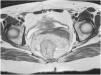

A 34-year-old woman had illness onset nine years earlier, with intermittent rectorrhagia, mucus in stools, and iron-deficiency anemia. Subtotal colectomy with ileorectal anastomosis was performed due to suspicion of ulcerative colitis. She underwent blood transfusions at her check-up appointments because of persistent bleeding and was hospitalized for stabilization and study. Upper gastrointestinal endoscopy was normal, and colonoscopy showed thinned mucosa, edema and erythema, friability, multiple violet-blue vascular dilations of 5-15 mm that extended into the inferior and middle thirds of the rectum, and a normal ileorectal anastomosis (Fig. 1). Magnetic resonance imaging revealed concentric thickening of the mesorectum, with no pelvic invasion, and a rectal wall measuring 16 mm (Fig. 2). In addition to the thickening of the rectal wall, a computed tomography scan identified tortuosity of an accessory artery emerging from the aorta and phleboliths in the pelvis (Fig. 3). Surgical treatment is proctectomy and ileoanal anastomosis, with a protective ileostomy. The patient signed a statement of her informed decision to refuse the procedure and accepted conservative treatment, which consisted of transcatheter embolization through angiography, the administration of microparticles containing 200 μm of polyvinyl alcohol, and the placement of a coil (Fig. 4). The patient is currently asymptomatic and under medical surveillance.